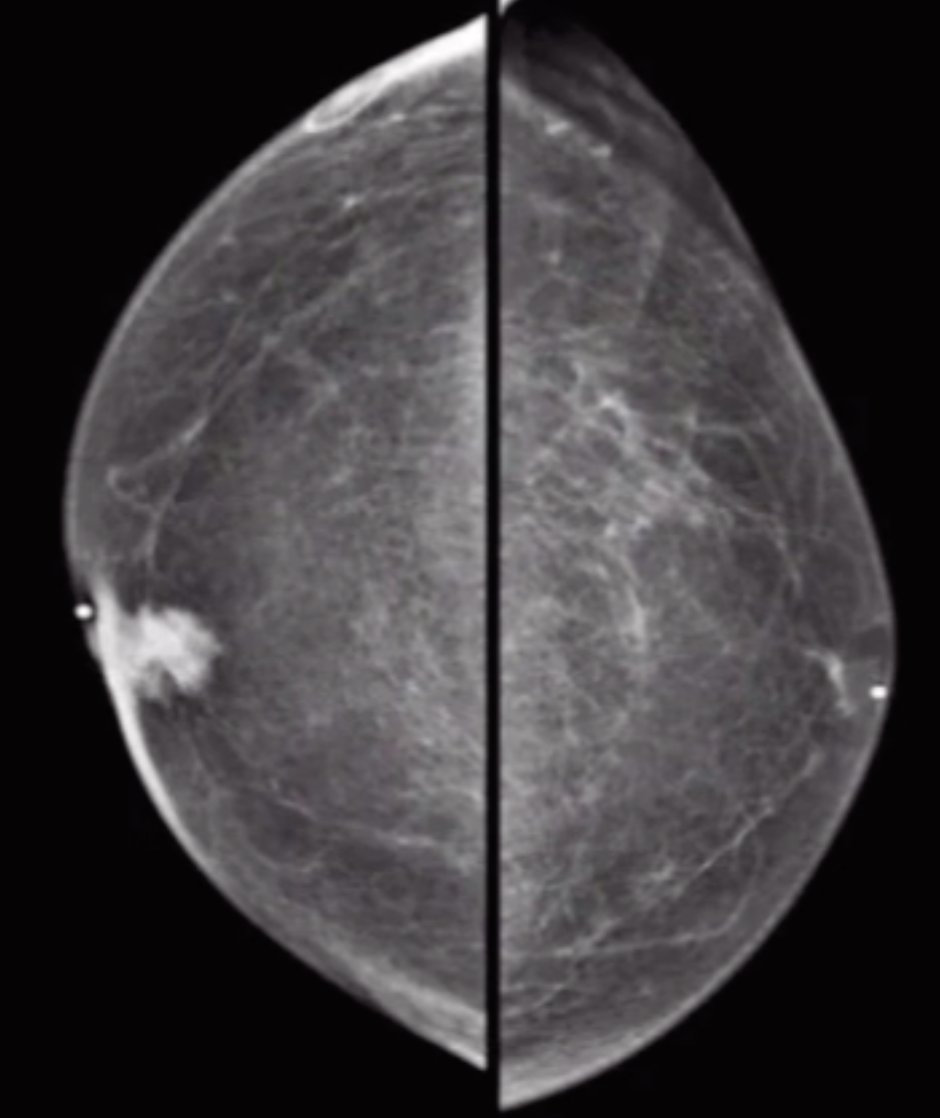

Breast Cancer

• Skin thickening with asymmetric breast mass

• Always ductal cancer

• Usually a spiculated mass

• Calcifications may be present

• Fat does not intercalate with the mass as much

• Usually in men ~70 yo